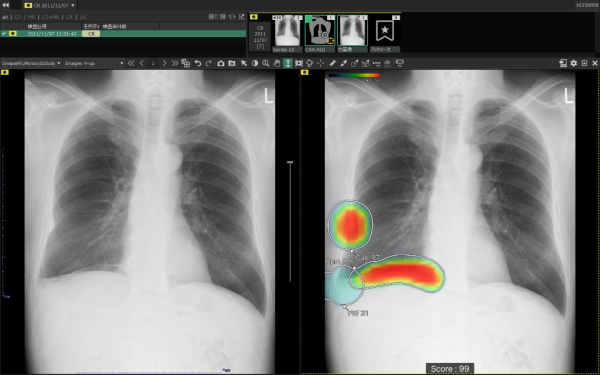

ヒートマップ/輪郭表示機能

異常所見の存在可能性(確信度)を、青から赤へのグラデーションで示すヒートマップ表示について、多くの利用者からご好評いただいている。一方、モノクロモニタを利用する一部の読影環境では、淡いヒートマップが確認しにくいという課題があった。新バージョンでは、異常所見の疑われる領域の表示方法として、「ヒートマップ表示」「輪郭表示」「ヒートマップと輪郭の併用表示」の3つの表示パターンが選択可能になった。これにより、各施設の運用環境に応じた最適な表示方法を利用できる。

所見名/スコア表示機能

従来のバージョンでは、複数の異常所見を検出した場合、検出された異常所見のうち最も確信度が高い所見のスコアのみを表示しており、各所見のスコアを確認したいという要望があった。新バージョンでは、各検出領域に対応する所見名と確信度を示すスコアを個別に表示できるようになった。これにより、医師は複数の異常所見について詳しい情報をひと目で把握でき、正確な診断を行うことが期待できる。